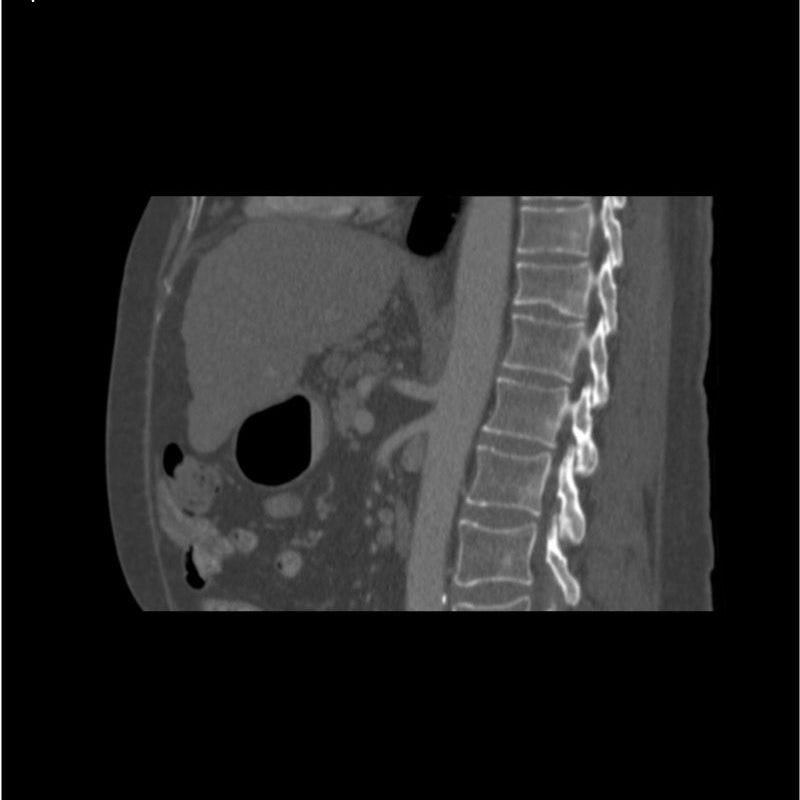

abdomen in portal venous phase. It covers the tenth thoracic vertebra to the third lumbar vertebra. The phantom represents an abdomen after cholecystectomy with small clips. The liver has typical signs of cirrhosis and there is an inferior vena cava filter implanted at the level of the third lumbar vertebra. Both kidneys have cystic lesions and there is a small kidney stone on the left side.

Realistic simulation of vasculature, bone and soft tissues, including the liver, pancreas, spleen, adrenals, kidneys, stomach, small intestine and colon.

- Liver cirrhosis

- cholecystectomy

- inferior vena cava filter

- kidney cysts

- kidney stone

- lymph nodes.